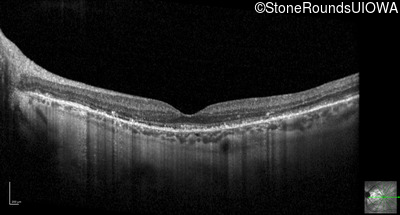

Optical Coherence Tomography - Left - 20/25 +3

Exemplar / OCT Stack